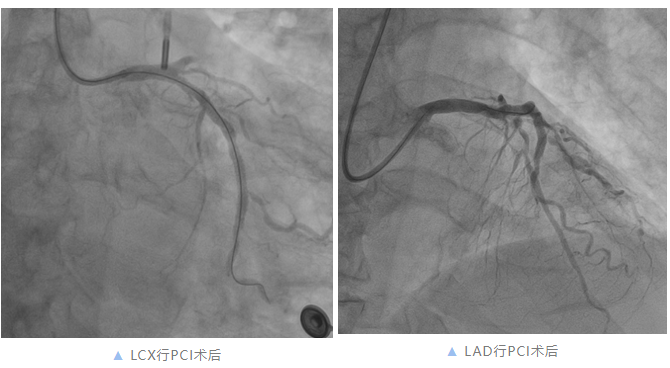

手术中,突发情况再次发生。霍大伯突发气促、咳粉红色泡沫痰,不能配合手术。与家属沟通后,立即给予咪达唑仑静脉泵入镇静、无创呼吸机辅助通气,并行主动脉球囊反搏(IABP)辅助支持。术中血压、心率突然下降,考虑心源性休克,立即给与阿托品0.5mg、多巴胺5mg静脉推注,再造影提示LCX近段闭塞,立即送Fielder XT导丝至LCX,行球囊扩张后于近段植入3.5*29mm支架1枚,患者血压、心率恢复。期间患者血压、心率再次突然下降,再造影提示LCX中远段急性闭塞,遂立即于LCX中远段行球囊扩张,考虑有高凝状态,给予替罗非班10ml冠脉内推注,并于中段植入3.0*25mm支架,在近段中段两支架连接处行后扩张,随后对LCX远段重度狭窄处行药物球囊扩张,LCX血流恢复,患者血压、心率恢复。

据《急性ST段抬高型心肌梗死诊断和治疗指南(2019)》,合并多支血管病变STEMI患者,行急诊IRA血运重建同时,可根据非IRA病变严重程度和供血范围同期行血运重建,也可考虑出院前对非IRA病变行血运重建(Ⅱa,B),综合考虑患者急性广泛前壁心肌梗死合并急性肺水肿、心源性休克,LAD由LCX提供逆向血流,LCX至LAD近中段血流时间明显延长,一旦LCX再次闭塞LAD无血流供应,随时猝死,遂决定同时开通LAD慢性闭塞病变。

李龙虎主任医师在微导管支撑下,灵活运用多种导丝逐渐通过LAD近段闭塞处至D1远段,并行球囊扩张,再造影提示LAD前向血流恢复TIMI3级。

手术效果: